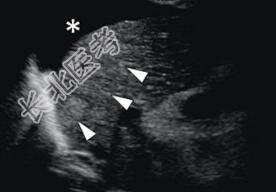

辅助检查:胃镜:胃窦癌,病理提示胃窦腺癌;腹部CT:肝硬化、大量腹水、胆总管下端小结石、胆总管结石、右肾结石。彩超:腹腔积液(少到中量)、腹主动脉脐上下处增宽壁增宽